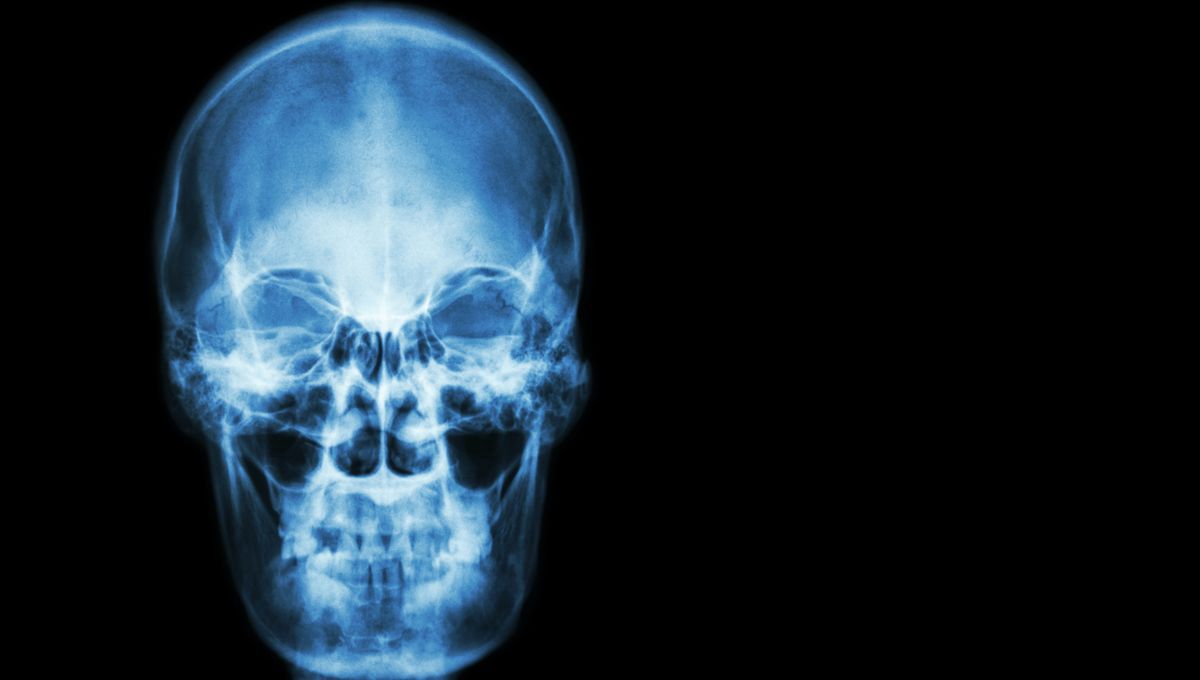

Hamman's Crunch: A Man Covered His Nose And Mouth Whilst Sneezing And Ended Up In Hospital

The "popping sensation" he felt is why you shouldn't cover your nose and your mouth while you sneeze.